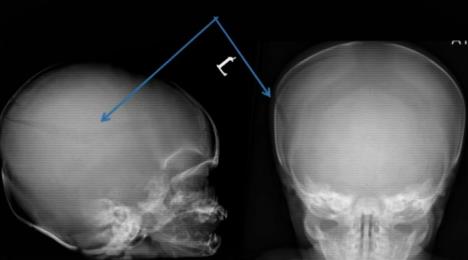

Naime, beba stara svega 24 dana umrla je od posledica preloma lobanje i izliva krvi u mozak 28. marta 2017. Pored toga, maleni Stenli je imao čak 32 preloma rebara i devet preloma ruku i nogu, koje je zadobio u najmanje tri odvojena incidenta.